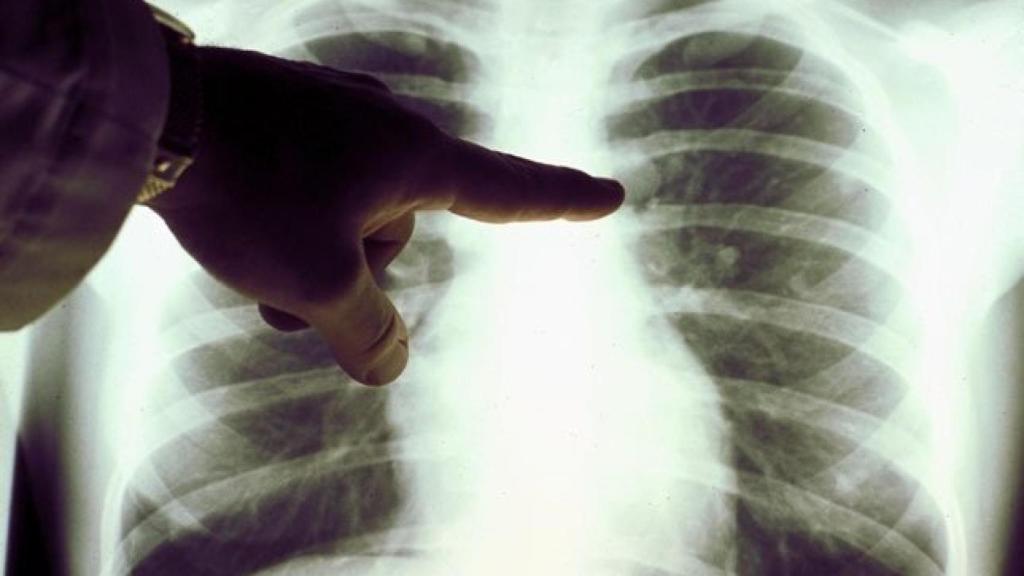

El cáncer más frecuente entre los tumores estudiados ha sido el de pulmón

Sí había un tipo de tumor con mayor representación era el de pulmón. De los 30 pacientes del estudio, 12 tenían un cáncer de pulmón de células no pequeñas, uno de los más comunes de esta patología. Cinco de ellos controlaron la progresión durante medio año como mínimo.